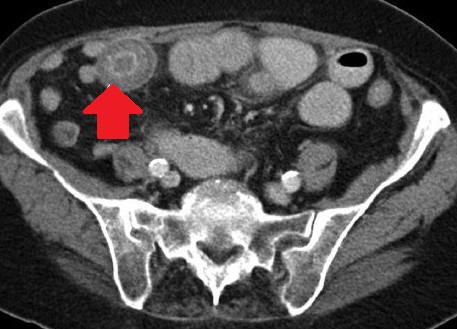

Abdominal CT scan. Distended small bowel loops with fluid content (Courtesy Dr. V. Penopoulos)